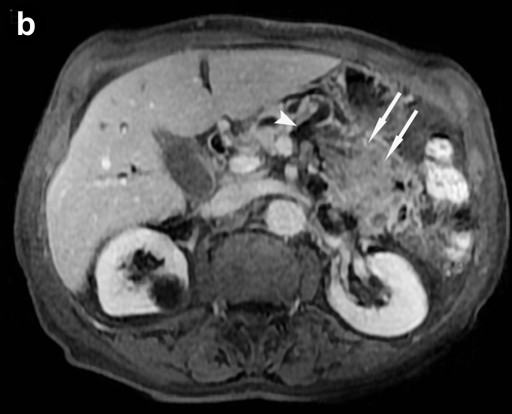

MRI (Signa EchoSpeed EXCITE HD, 1.5 Tesla, GE Healthcare, Waukesha, WI, U.S.A.) was performed and showed two mainly cystic tumors in the pancreatic head and tail with low intensity in T1-weighted images and high intensity in T2-weighted images. The intracystic solid tumor nodules were T1 and T2 hypointense and showed an intensive early, focal gadolinium uptake on dynamic contrast-enhanced T1-weighted images (Figure 2ab). T1-weighted contrast-enhanced images, T2-weighted images, and magnetic resonance cholangiopancreatography (MRCP) clearly depicted the communication between the two separate tumors and the pancreatic duct (Figure 2c).

Figure 2. a. Axial T2-weighted image at the level of the pancreas shows the manifestation of the intraductal oncocytic papillary neoplasm in the pancreatic tail. Communication to the pancreatic duct can be identified (arrowhead) as well as the hypointense solid tumor parts (arrows). b. Axial T1-weighted image after contrast enhancement with gadolinium at the same level also shows communication to the pancreatic duct and strong enhancement of the solid tumor parts (arrows). c. MRCP clearly depicts communication of the dilated pancreatic duct (pd) with the intraductal oncocytic papillary neoplasm in the pancreatic head (asterisk) and tail (arrowhead); the solid tumor components are observable. (bd: dilated common bile duct). |